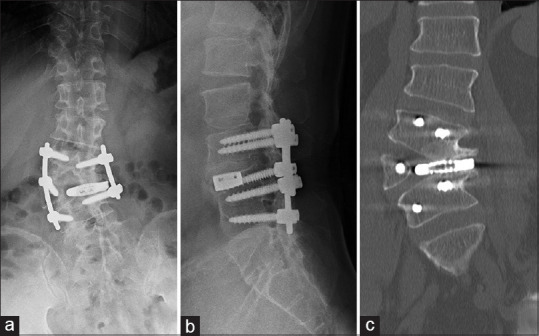

Hemivertebra is a rare congenital spinal anomaly often diagnosed in childhood due to progressive scoliosis. Initial diagnosis of hemivertebra in adulthood is uncommon, and standardized treatment protocols are not well established. This report presents a case of successful management of an L4 hemivertebra in an adult using oblique lateral interbody fusion (OLIF) with O-arm navigation. The patient, a 55-year-old, presented with chronic lower back pain and thigh pain exacerbated by standing and walking. Imaging studies revealed an L4 hemivertebra with mild scoliosis and foraminal stenosis caused by degenerative change. The patient underwent OLIF with O-arm navigation, followed by short-segment fixation with pedicle screws. Postoperative imaging confirmed appropriate implant positioning. The patient experienced complete resolution of symptoms except for mild sensory disturbance in the left thigh, with stable outcomes at the 2-year follow-up. The OLIF technique, guided by O-arm navigation, allowed precise adjustments to the anatomical characteristics of the hemivertebra, minimizing surgical invasion, and avoiding extensive corrective fixation. This approach resulted in favorable outcomes, suggesting its viability as a treatment for adult hemivertebra with minimal scoliosis. Furthermore, the use of intraoperative navigation addressed the anatomical abnormalities associated with adult hemivertebra, reducing the reliance on repeated fluoroscopic imaging and minimizing the risk of complications. OLIF with O-arm navigation is an effective and minimally invasive treatment option for adult hemivertebra, providing symptom relief and favorable outcomes.